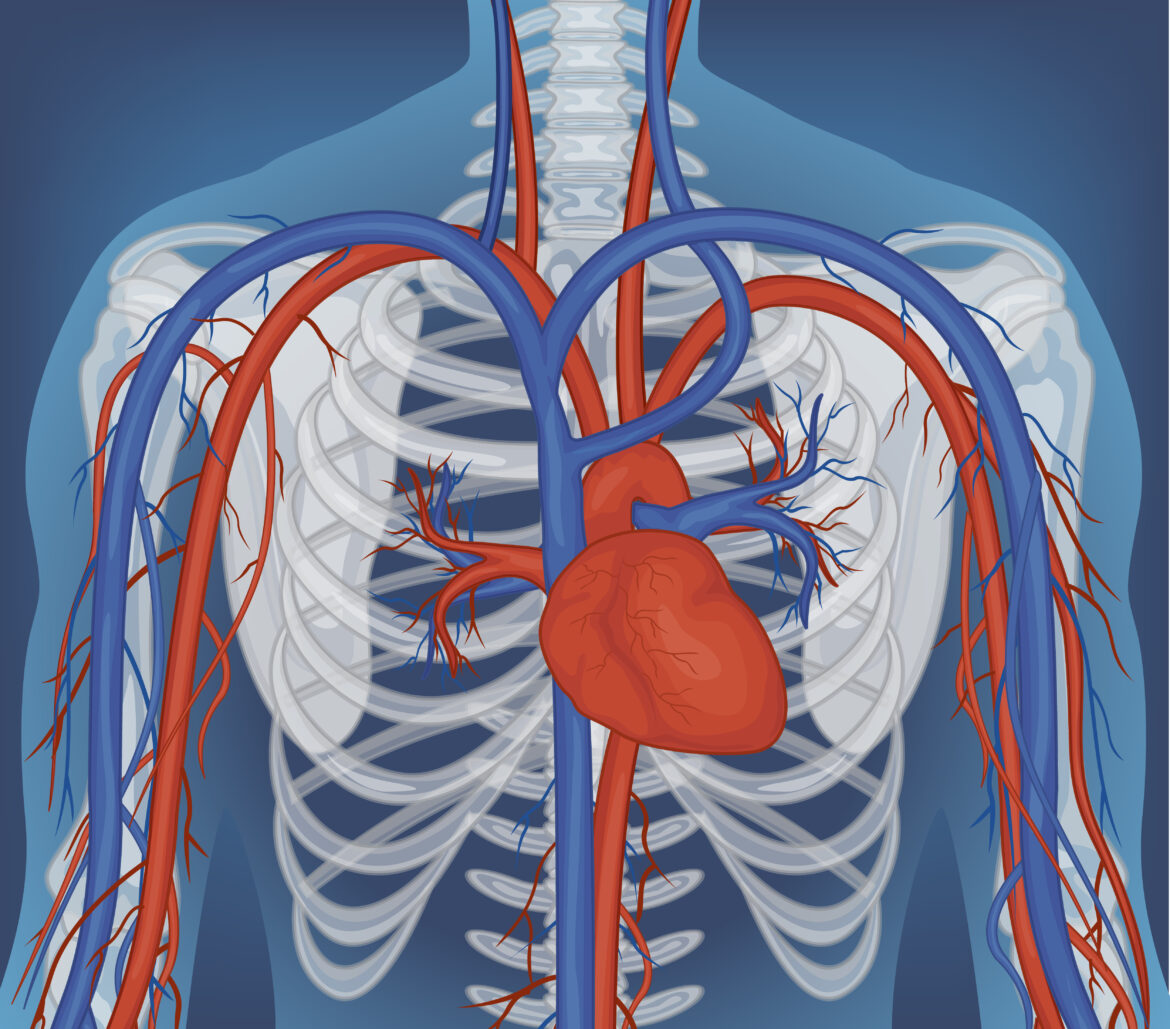

You may have heard that the circulatory system is a flow tube that pumps blood from the heart, through the arteries, making the blood flow, and then back through the veins to the heart. However, the veins do not return blood to the heart by simple passive flow; the skeletal muscle in our bodies is primarily responsible for returning blood from our legs to the heart. To return blood to the heart against the upward pull of gravity, it requires high pressure contractions of muscles surrounding the deep veins. Specifically, the calf muscles have a function of the muscle squeezing the blood in order to pump it up against gravity to the heart. This peripheral pump is essential for the circulatory system to function.

When the calf contracts during walking, running, or any rhythmic lower limb activity, the muscle compresses these deep veins. Venous valves open upward and close downward, so the compressed blood moves toward the heart rather than flowing back down. The National Institutes of Health has published extensive material on the physiology of venous return, and the skeletal muscle pump is consistently described as the dominant mechanism for moving blood out of the legs against gravity (NIH on circulation).

In the healthy adult, the muscles, veins and blood vessels are arranged in a functional system that permits a person to walk for hours each day without developing painful swelling of the lower legs.

The underlying message is that the skeletal muscle pump is not a peripheral detail of lower limb anatomy. It is the primary mechanism by which blood gets back to the heart from the feet and lower legs, and it is structurally dependent on the muscles, joints, and movement patterns that bodyworkers spend their careers studying.

Venous return from the lower limbs is as much a musculoskeletal event as it is a cardiovascular event. The calf muscle pump involves the gastrocnemius and soleus muscles and the ankle joint, and is primarily controlled by muscle contraction. The influence of decreased muscle tone, reduced joint mobility, and aberrant movement habit on lower limb venous return are discussed.